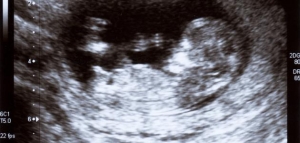

أعراض الحمل في الشهر الأول

تختلف أعراض الحمل بين امرأة وأخرى، كما يختلف وقت ظهور أعراض الحمل بين امرأة وأخرى؛ فهناك من تظهر عليهنّ أولى علامات الحمل بعده بأسبوع إلى أسبوعين منه، لكن هناك من لا يشعرن بأيّة أعراض خلال الأشهر القليلة الأولى.[١]